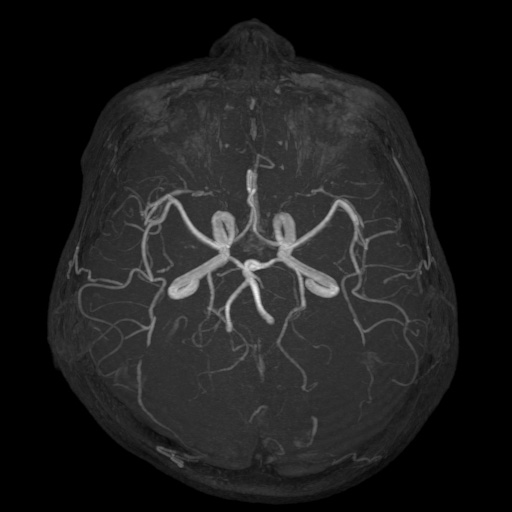

MRA検査

MRIの撮影技術を使って、血管を描出する方法です。頭蓋内外の重要な動脈(総頸動脈、内頸動脈、ウィリス輪、椎骨動脈、脳底動脈)の変化をとらえることができます。

MRIではCT検査と同様、腫瘍の大きさや形、数などがわかります。また、MRAでは脳動脈瘤、脳梗塞、脳動静脈奇形、もやもや病、閉塞性動脈病変などの脳血管障害がわかります。脳ドックでは、くも膜下出血の原因となる脳動脈瘤のスクリーニング検査としてよく用いられています。